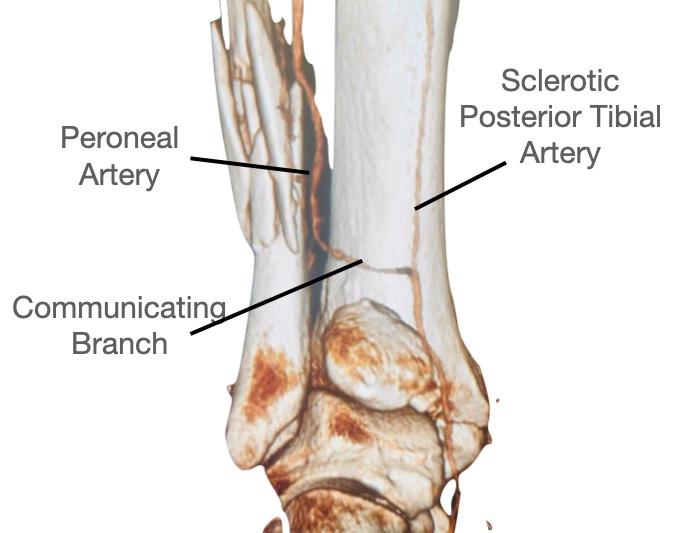

Vascular studies have shown two important aspects regarding the risks posed by the PL approach3. Firstly, the flexor hallucis longus (FHL) muscle is supplied by up to six perforators from the peroneal artery. By moving the FHL medially to get access to the posterior tibia during the PL approach, the FHL is moved away from the peroneal artery and can therefore lose its blood supply and become necrotic. If you have seen a FHL contracture following a PMF fixation, this is the reason.

Lyndon Mason Consultant, NHS University Hospitals of Liverpool Group; Honorary Associate Professor, University of Liverpool

The risk increases, the longer the incision. Secondly, and more importantly, in a twovessel limb (dominant peroneal artery and anterior tibial), the blood supply to the foot is supplied by a communicating vessel connecting the peroneal and tibial arteries (figure 3). This communicating branch is very commonly sacrificed in the PL approach If this is sacrificed in a two vessel limb, this can result in an avascular foot4. The MPM comes anterior to the FHL and communicating branch and does not have these risks.

The MPM approach overcomes the three principal limitations of PL approach, restricted exposure, unaddressed entrapment, and vascular risk. Its direct vision of the posterior and medial tibia enables true anatomical reduction, particularly in die-punch and 2B PMFs. The ability to clear PTT entrapment prevents secondary displacement and pain. Preservation of the posterior vasculature markedly decreases complication rates. Adoption requires anatomical familiarity, but reproducibility and outcomes justify its broader implementation. In my view, due the vascular risks of the PL approach specific to a two-vessel limb, continued use of the PL approach should instigate a CT angiogram pre-surgery.

Figure 3: CT angiogram pre fixation of a PMF, showing a 2-vessel leg due to sclerosis of the posterior tibial artery, where the peroneal artery becomes dominant through the communicating branch.